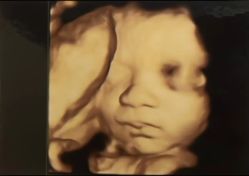

白玉 上传于 25-09-05 | 报错

• -深圳港龙妇产医院

相册